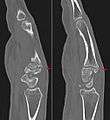

Carpal boss in plain X-Ray.

Carpal boss in CT.